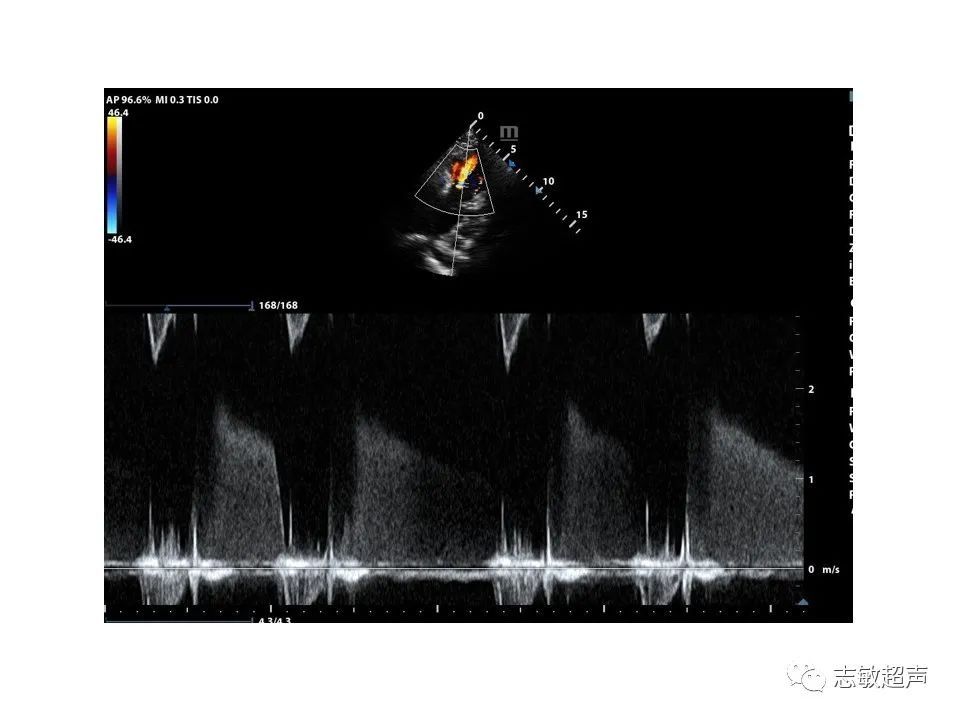

2.肺动脉主干内旋流